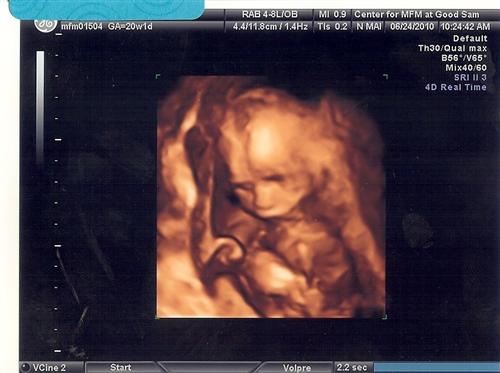

Back from my level 2!!!!!! (with pics)

I would 1st like to thank everyone for their good wishes. Everything is 100% perfect with the baby and it is measuring perfectly from every aspect. Estimated weight is 12ounces so far. They did up my dose of insulin, but are thrilled with how this pregnancy has progressed thus far. The best news is that my cervix has closed!!!

Now here are some pics...

3d

and yes, we caved! It is definitely 100%.......